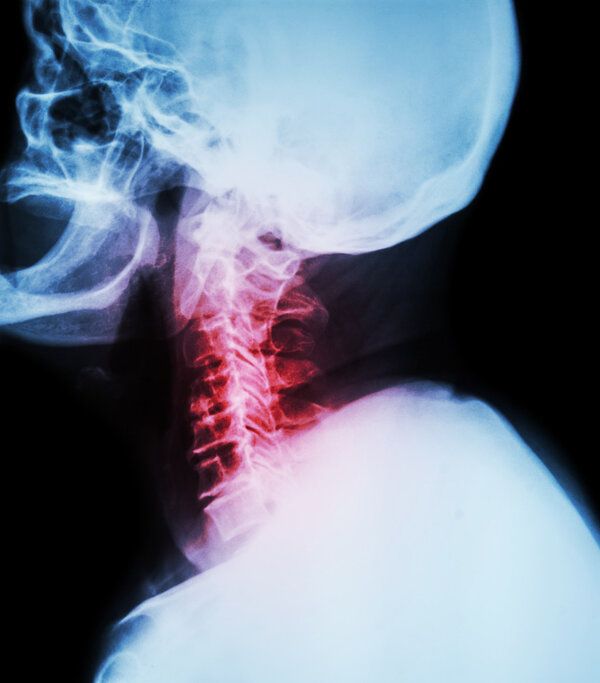

4種常見的頸椎手術(shù)名稱

核心提示:四種常見的頸椎手術(shù)包括前路減壓融合術(shù)、后路減壓術(shù)、椎間孔鏡下微創(chuàng)手術(shù)和經(jīng)皮穿刺椎間盤切開器治療。 上述四種頸椎手術(shù)均針對不同類型的頸椎病變。前路減壓融合術(shù)適用于頸椎管狹窄癥;后路減壓術(shù)針對多節(jié)段脊髓壓

四種常見的頸椎手術(shù)包括前路減壓融合術(shù)、后路減壓術(shù)、椎間孔鏡下微創(chuàng)手術(shù)和經(jīng)皮穿刺椎間盤切開器治療。

上述四種頸椎手術(shù)均針對不同類型的頸椎病變。前路減壓融合術(shù)適用于頸椎管狹窄癥;后路減壓術(shù)針對多節(jié)段脊髓壓迫;而椎間孔鏡下微創(chuàng)手術(shù)與經(jīng)皮穿刺椎間盤切開器治療則分別針對特定的神經(jīng)根型頸椎病和突出性頸椎病。這些手術(shù)旨在緩解因各種原因?qū)е碌念i部疼痛、肩背酸痛、肢體麻木無力等癥狀。其中,前路減壓融合術(shù)可減輕由于頸椎管狹窄引起的上肢麻木、行走不穩(wěn)等癥狀;而后路減壓術(shù)則有助于改善由多節(jié)段脊髓壓迫所致的下肢無力、行走困難等問題。

常規(guī)影像學(xué)檢查如X光片、MRI或CT掃描是必需的,以評估頸椎結(jié)構(gòu)并排除潛在風(fēng)險。此外,可能還需要進行神經(jīng)系統(tǒng)功能測試,例如肌電圖或神經(jīng)傳導(dǎo)速度測試,以確定是否存在神經(jīng)損傷。具體的治療方法需根據(jù)患者的具體情況制定,但通常包括物理療法、藥物治療等非手術(shù)措施。對于存在明確手術(shù)指征者,上述四種手術(shù)可能是有效的解決方案。